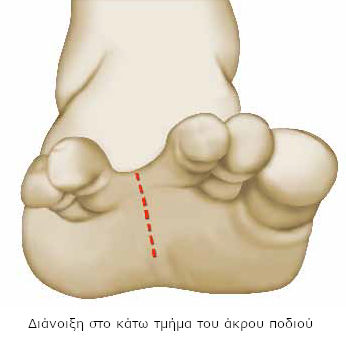

Η τομή μπορεί να γίνει στο άνω ή κάτω τμήμα του άκρου ποδιού. Συνήθως η διάνοιξη πραγματοποιείται ανάμεσα στους δακτύλους, στην κοιλότητα που δημιουργείται στη βάση τους, στο κάτω τμήμα.